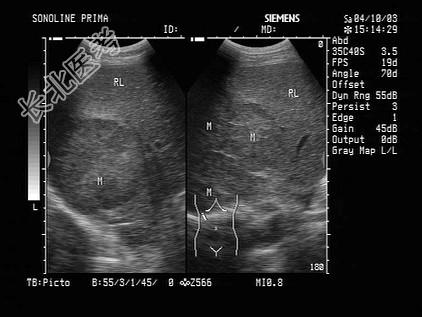

- 单项选择题男性患者,35岁, 乙肝带菌者,体检时发现肝部异常光团, 如图可诊断为   (   )

A、多发肝血管瘤

B、肝囊肿

C、肝转移癌

D、肝脓肿

E、肝癌